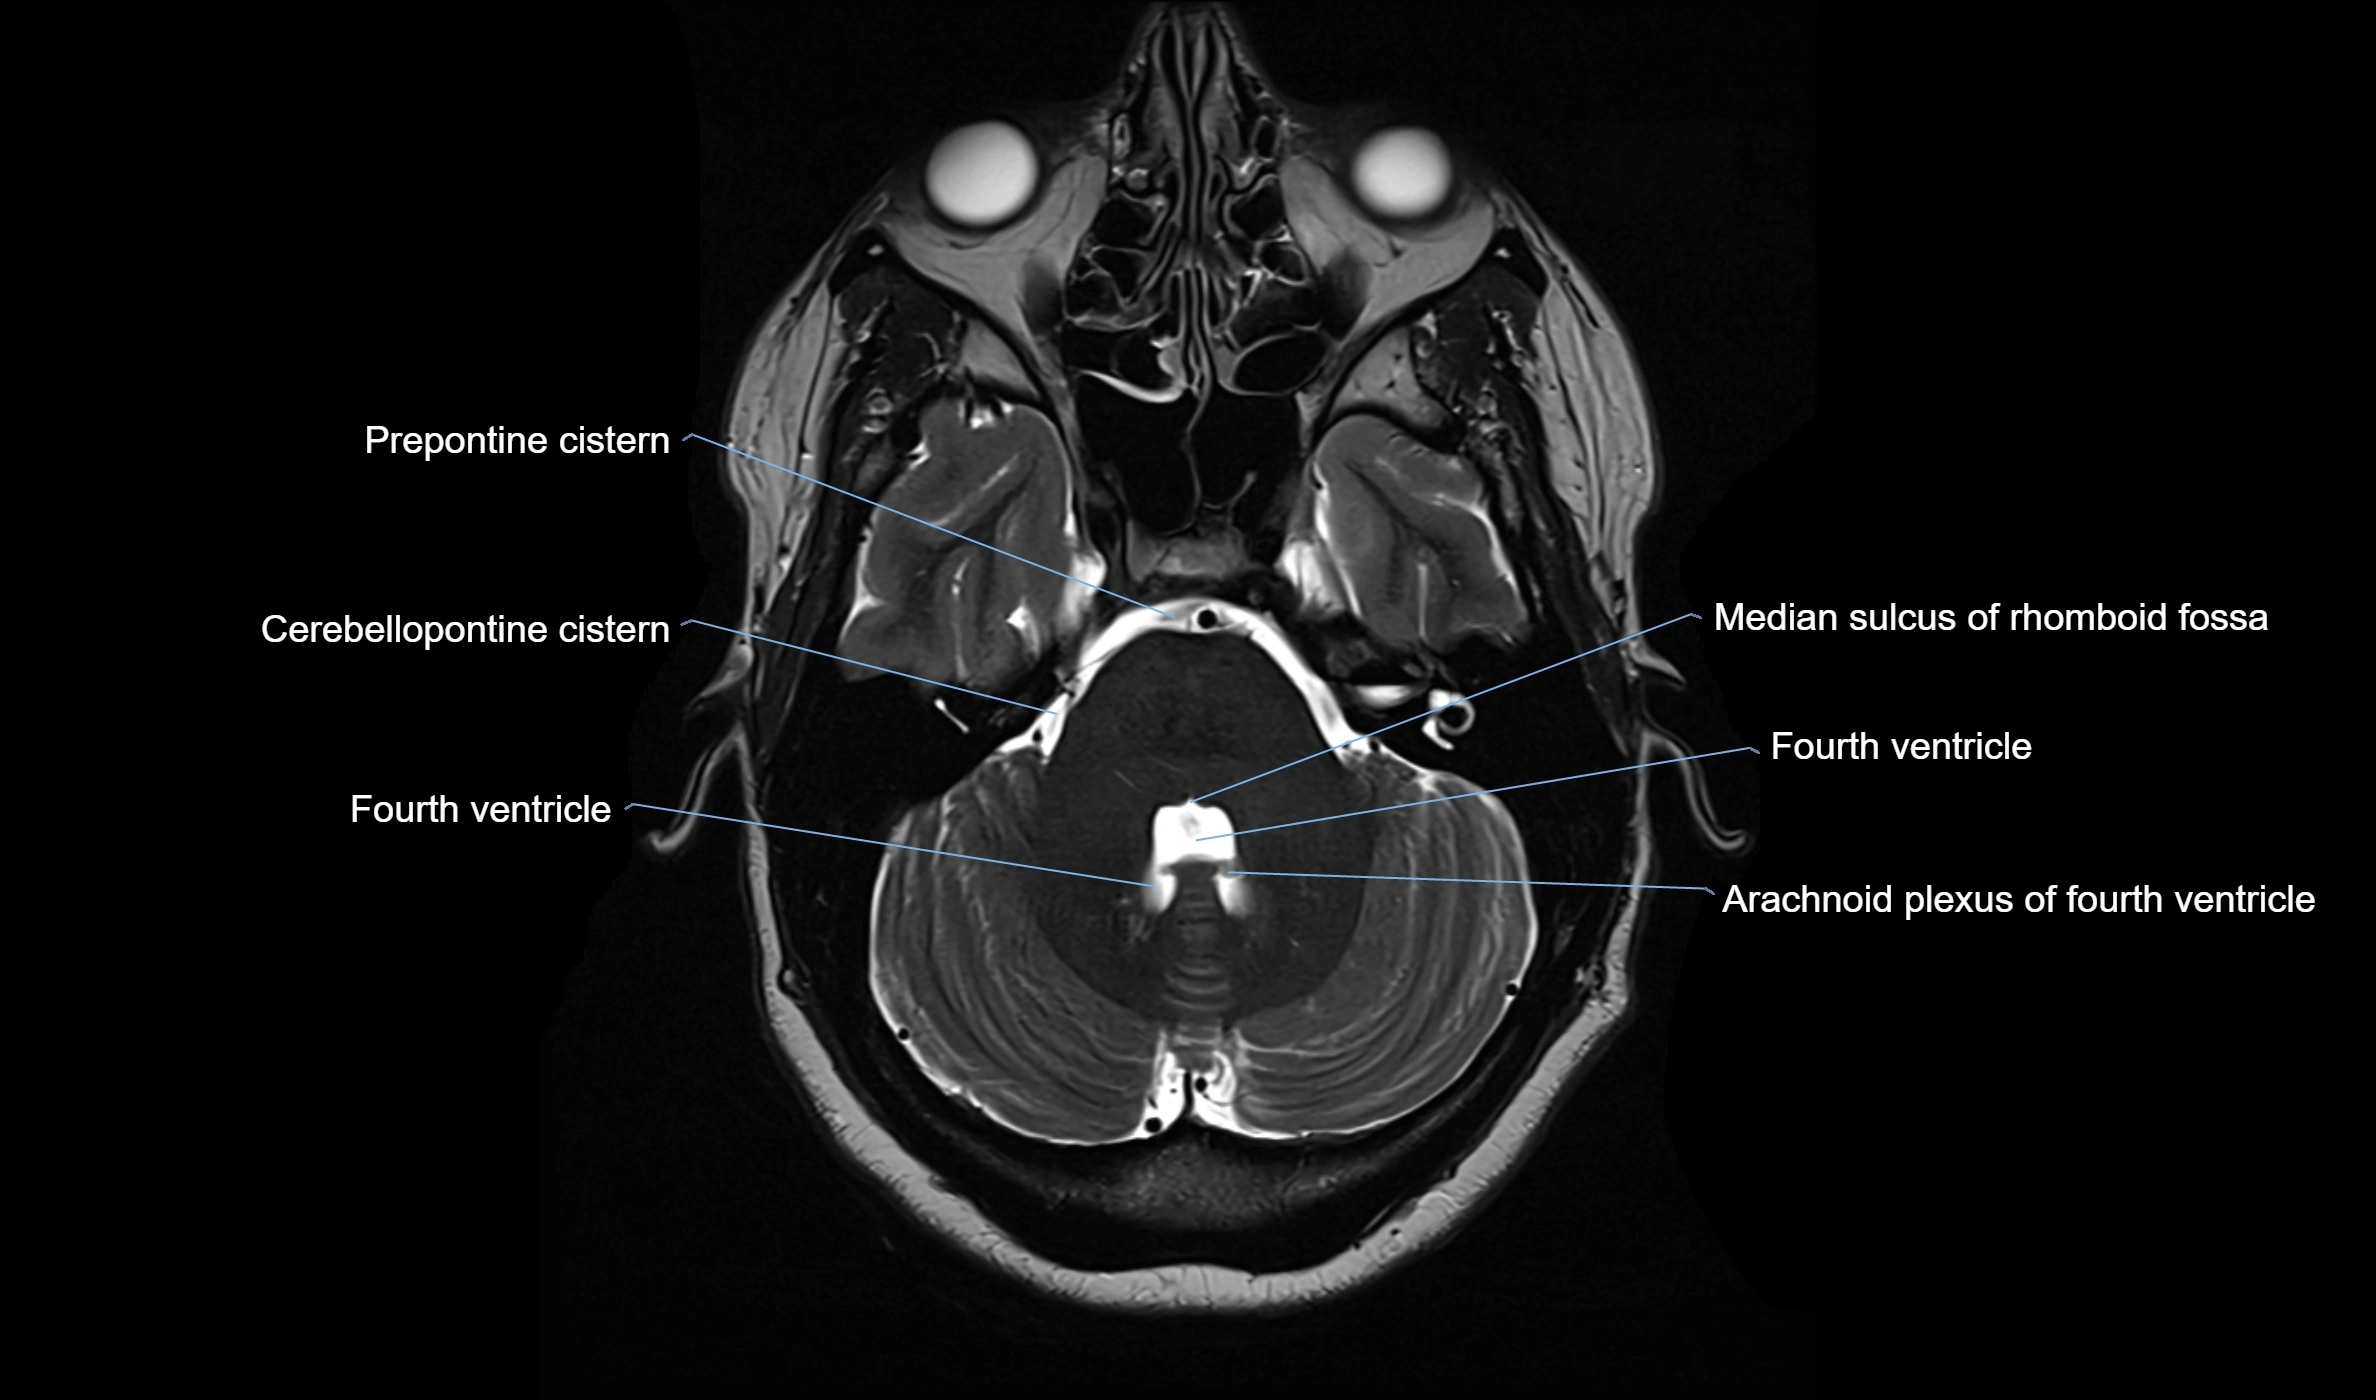

Ambient cistern

The ambient cistern is a paired, narrow, and elongated subarachnoid space located bilaterally along the lateral aspect of the midbrain. It serves as a conduit between the interpeduncular cistern anteriorly and the quadrigeminal cistern posteriorly. This cistern houses critical neurovascular structures, including parts of the posterior cerebral artery, superior cerebellar artery, trochlear nerve (cranial nerve IV), and the basal vein of Rosenthal. It plays an important role in the circulation of cerebrospinal fluid (CSF) and provides an anatomical corridor for various vessels and nerves passing around the midbrain.

MRI Appearance

• T2-weighted images:

• The cistern is hyperintense (bright) due to the high water content of CSF.

• Encapsulated vessels and nerves are seen as flow voids or hypointense lines within the bright background.

CT Appearance

• The ambient cistern is visualized as a low-density (hypodense) area, similar to other CSF-filled spaces, lateral to the midbrain.

• Blood, masses, or increased attenuation in the cistern may suggest pathology (e.g., subarachnoid hemorrhage, mass effect from tumors or edema).

• Loss of normal cistern outline can indicate mass effect, brain swelling, or herniation.